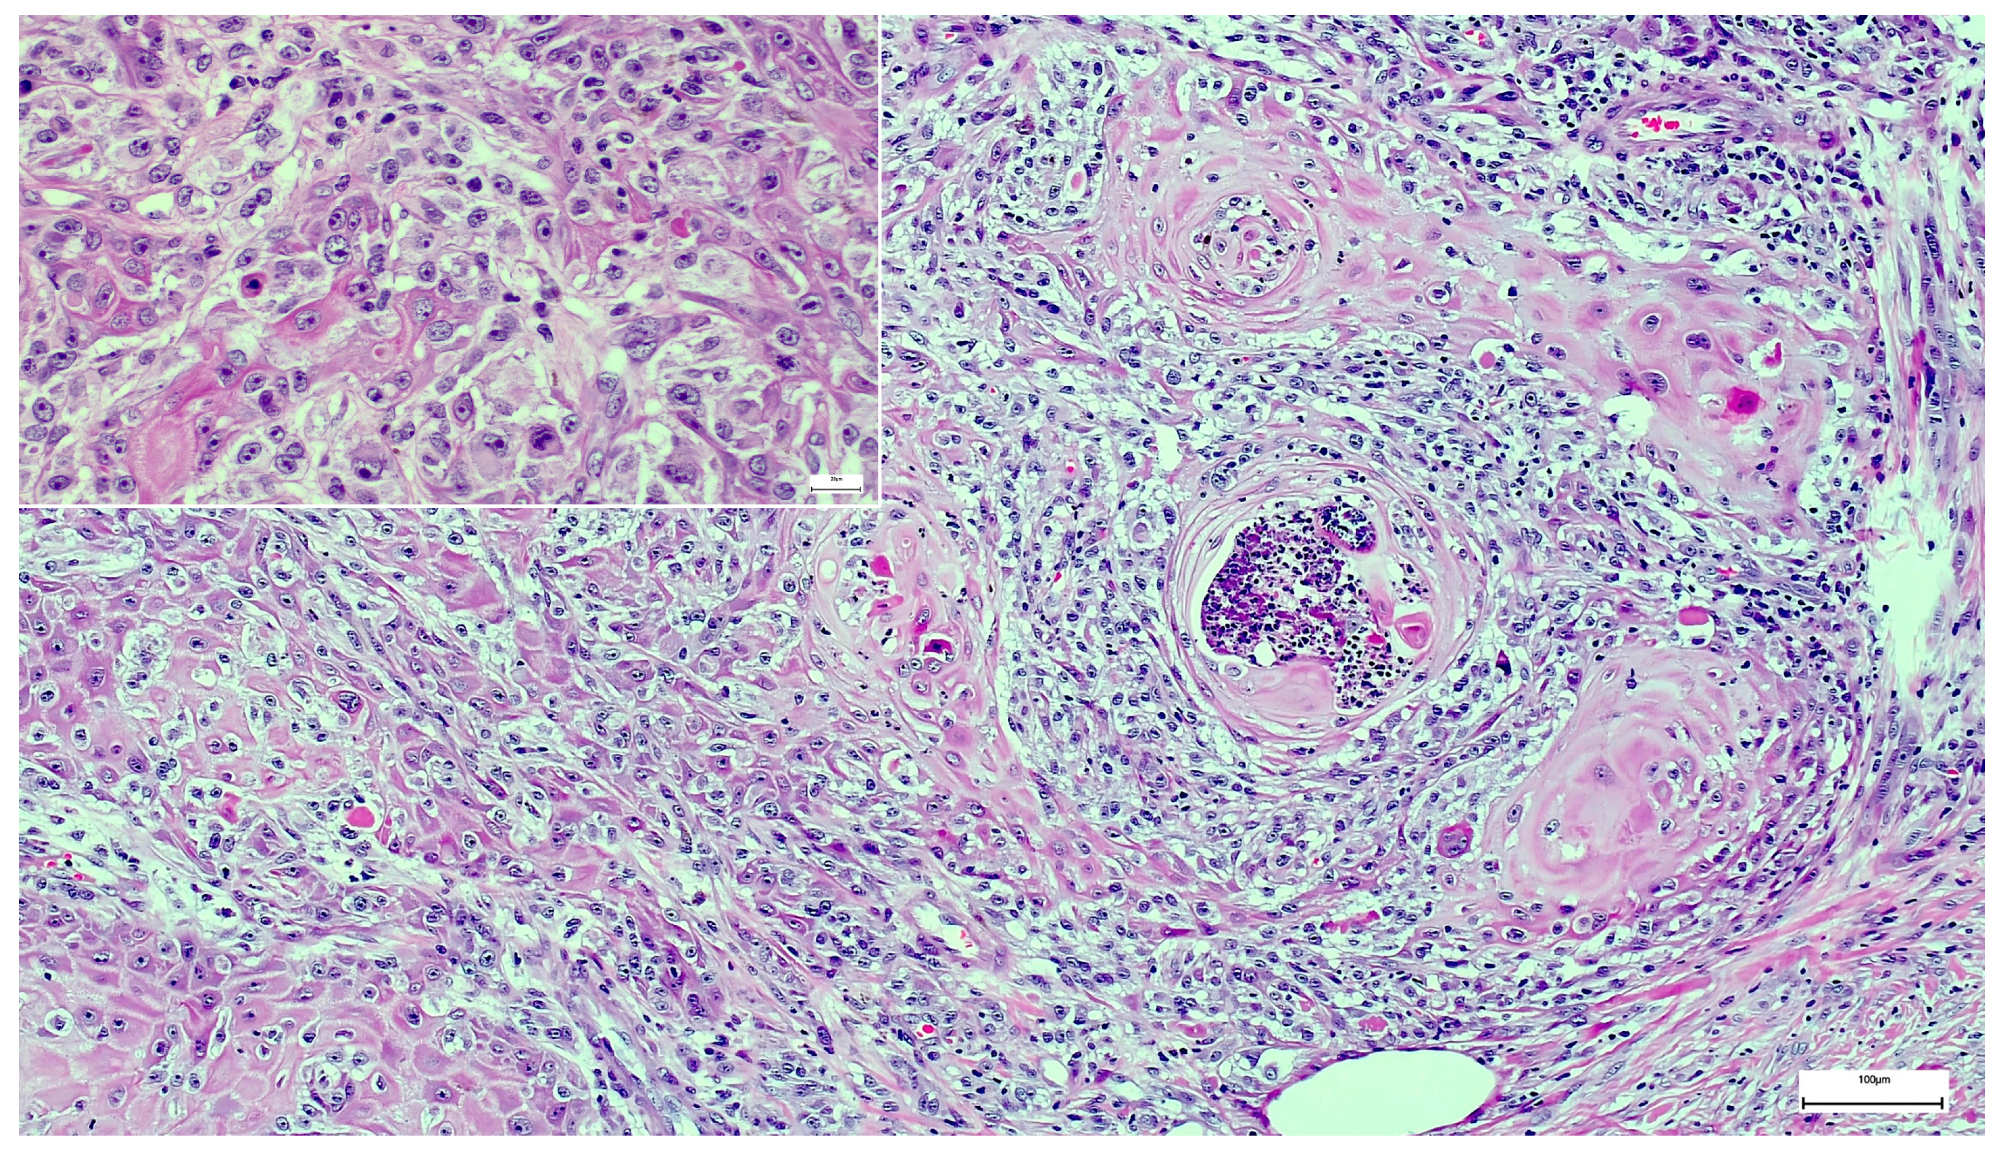

A Wolf in Sheep’s Clothing: Collision of Melanoma and Keratoacanthoma

:1. Case Presentation